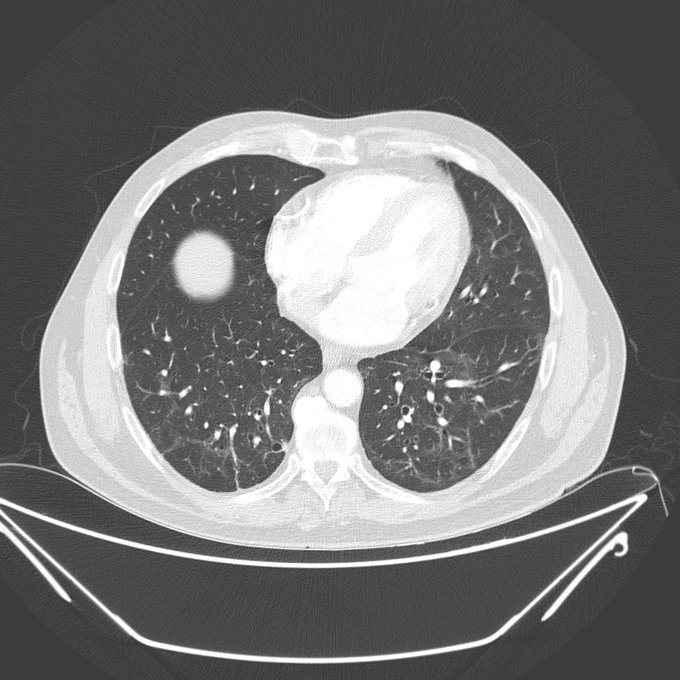

ddianın kaynağı, doğrudan tekil hasta verilerine dayanıyor. Radyoloji uzmanı ve Üsküdar Üniversitesi akademisyeni Prof. Dr. Güner Sönmez’in Twitter hesabında gündeme getirdiği konuda, koronavirüse yakalandıktan sonra kanserli hücrelerinde azalma yaşanan hastaların örnekleri yer alıyor. Aynı zamanda yine Sönmez’in paylaştığı verilere göre kimi kanserli hastalarda koronavirüs tanısı ve tedavisi sonrası kemoterapiden verim alma oranında da artış yaşanmış.

Benzer örnekler yabancı kaynaklarda da yer alıyor. Birleşik Krallık’ta lenfoma teşhisi konan ve tedavi gören 61 yaşındaki bir hastanın koronavirüse yakalanması sonrası gerçekleşen tedavi sürecinin ardından çoklu tümörlerinin büyük oranda azaldığı biliniyor.

New York Rochester Üniversitesi Tıp Merkezi James P. Wilmot Kanser Enstitüsü Direktörü Dr. Jonathan Friedberg’e göre bu türden vakalarda yüzde 25 oranında remisyon görülebiliyor. Yani kanser hastalığına sahip kişilerde zaman zaman aktif kanser bulgusunun bulunmadığı zamanlar olabiliyor. Ancak Friedberg’e göre yukarıda bahsettiğimiz vakada daha agresif bir ilerleyiş var ve bu durumda remisyon görülmesi çok daha nadir bir durum. Bu da verileri önemli hale getiriyor.

Ağırlıklı olarak lenfoma ve akciğer kanseri hastaları üzerinden gelen verilerle ortaya atılan bu iddianın yanında aynı zamanda koronavirüse yakalanan kanser hastalarında ölüm oranının genel kitleye oranla yüzde 16 daha fazla olduğunu ortaya koyan veriler de var.